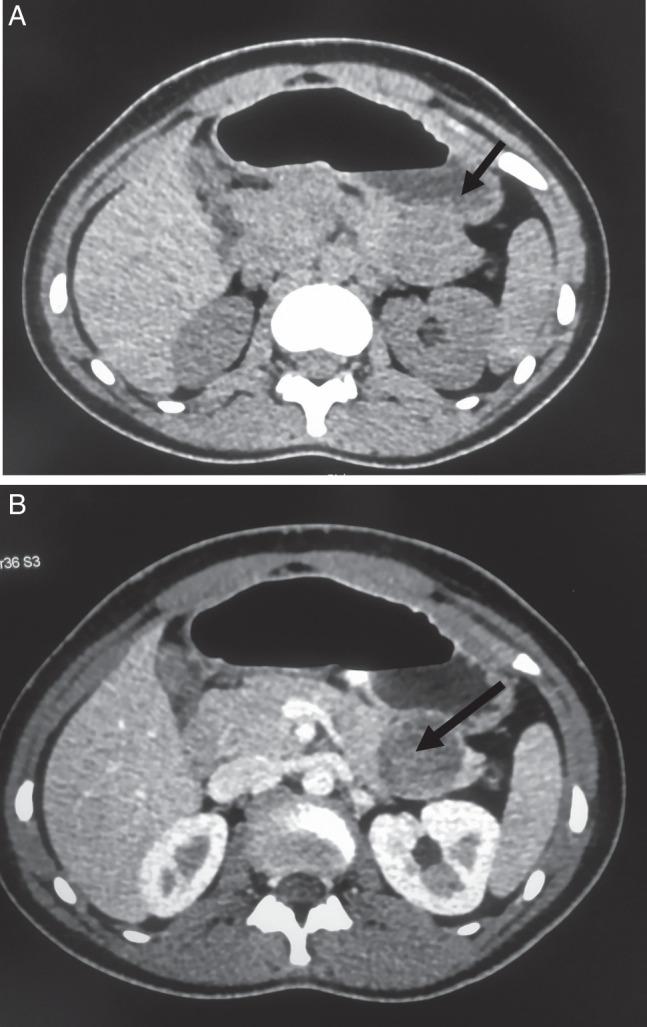

The authors have reported two cases of solid-pseudopapillary neoplasm of the pancreas with a median age of 12 years, both in females with abdominal pain.

Both cases are in females with different treatment modalities. The patient underwent distal pancreatectomy in the first case and enucleation of mass from the distal pancreas in the second case because the size of the tumor is 5 cm and does not involve the bile duct and major pancreatic duct.

The authors discussed two cases of solid-pseudopapillary neoplasm of the pancreas both in a 12-year-old female-both the patients presented with abdominal pain. The patient underwent a different treatment. The diagnosis was confirmed by radiological investigation through non-contrast and contrast CT and supported by histopathology findings.

作者报告了两例胰腺实性假乳头状肿瘤病例,中位年龄为12岁,均为女性,均有腹痛症状。

两例均为女性,采用了不同的治疗方式。第一例患者接受了胰体尾切除术,第二例患者因肿瘤大小为5厘米且未累及胆管和主胰管,故行胰体尾肿物剜除术。

作者讨论了两例12岁女性胰腺实性假乳头状肿瘤病例,两名患者均表现为腹痛。患者接受了不同的治疗。通过非增强和增强CT的影像学检查确诊,并得到组织病理学结果的支持。